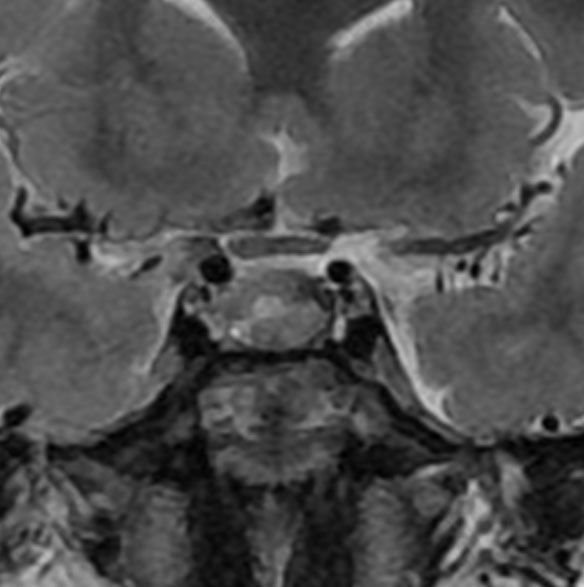

増大しても下垂体症状を出さなかった例

9歳の女の子に偶然発見された腫瘍です。何の症状もありませんでした。頭蓋咽頭腫と診断されて経過観察となりました。1年半観察しましたが腫瘍は増大して,視交差の変形が増して両耳側1/4半盲となり症候性となりました。下垂体機能は正常でした。

上のT2強調画像では,全体的に低信号で,高信号の部分が混在します。上右のCISS画像では,下垂体組織が右に変移していることが推定されます。